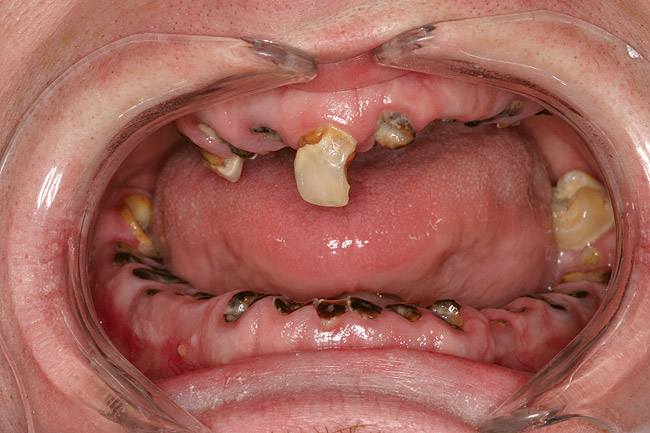

Figure 2  DEVASTATING EFFECTS When smoked, methamphetamine produces highly toxic and corrosive fumes of lithium, muriatic, and sulfuric acids that can destroy enamel rapidly. With continued use, methamphetamine can produce severe, rampant caries. When someone presents with rampant anterior lesions it should be a red flag for methamphetamine use.

Figure 2

When smoked, methamphetamine produces highly toxic and corrosive fumes of lithium, muriatic, and sulfuric acids that can destroy enamel rapidly. With continued use, methamphetamine can produce severe, rampant caries, similar to early childhood caries. Patients have reported noticing changes in the appearance of tooth structure in as little as 3 months of use. The affected surfaces are the buccal and labial smooth surfaces, as well as the interproximal surfaces (Figure 1 through Figure 3). Because in the general population the vast majority of decay is found in the posterior molars, when someone presents with rampant anterior lesions it should be a red flag for methamphetamine use.5

While high on the drug, users exhibit repetitive motor activities such as clenching and grinding of their teeth. This leads to severe attrition compounded by the chemical erosion from the toxic by-products produced from smoking the drug. Increased function further affects the periodontal health and can contribute to premature tooth loss.